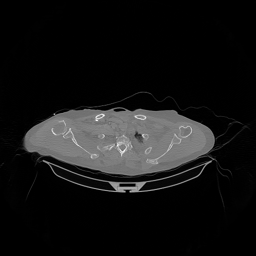

The results for simulated noisy data are shown in Fig. 2. The first and third rows display two representative slices from the test set, and the second and fourth rows present the corresponding error maps. The traditional WCE method suppresses cupping artifacts and recovers some missing anatomical structures but still shows noticeable deviations from the ground truth. Predictions from the four diffusion-based models demonstrate a markedly improved ability to restore anatomical structures. Among them, cDDPM fails to fully reconstruct the patient bed and retains residual noise in its outputs. This noise is attributable to an incomplete reverse denoising process rather than residual Poisson noise, as evidenced in our noise-free experiments (Fig. 5 in the Appendix). PatchDiffusion, diffusionGAN, and I2SB achieve similar visual quality, with I2SB producing the cleanest and most consistent reconstructions.

Quantitative results in Tab. V further confirm I2SB’s superiority over conventional deep learning methods such as FBPConvNet and Pix2pixGAN across RMSE, PSNR, and SSIM. Compared to other diffusion models—including cDDPM, PatchDiffusion, and cLDM—I2SB delivers higher image quality, while diffusionGAN achieves comparable quantitative performance. However, I2SB demonstrates a significant advantage in inference efficiency, as summarized in Tab. IV.